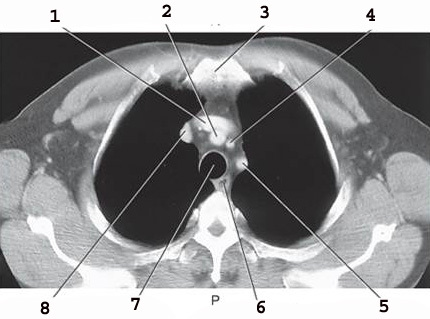

1

Rt brachiocephalic vein

2

brachiocephalic artery

3

L brachiocephalic Vein

4

L common carotid A

5

L subclavian artery

6

trachea

5 on the left

esophagus (there are 2 number 5’s)